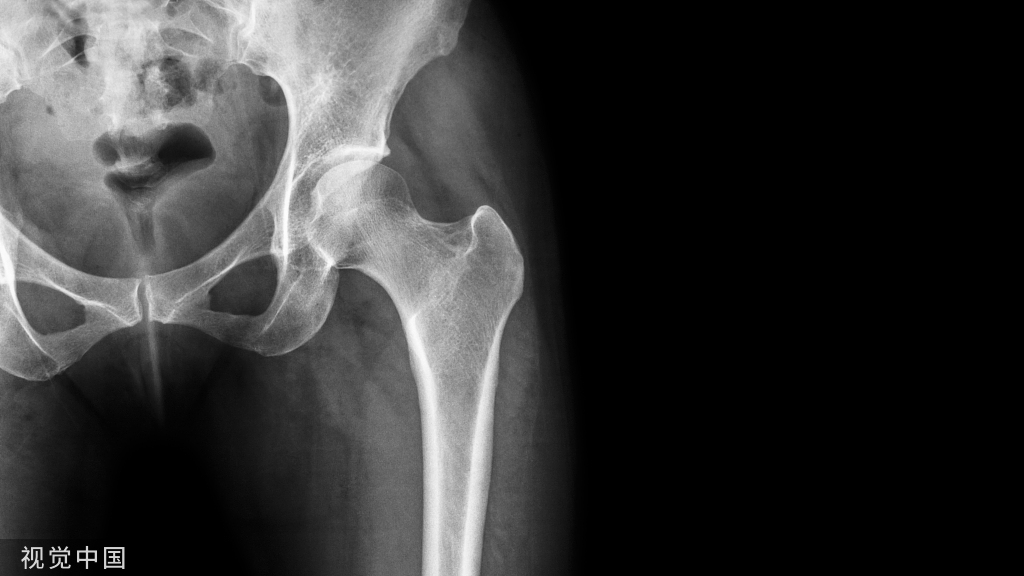

骨盆前后位 X 线片显示左侧股骨粗隆下骨折、右侧骶骨骨折、右侧耻骨支骨折和髂骨翼粉碎性骨折。左侧的跟骨板固定髂骨翼粉碎性骨折